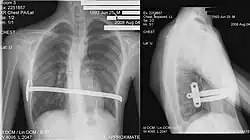

La technique chirurgicale mini-invasive de Nuss, plus récente[16], consiste à introduire une ou deux barres à l'intérieur de la cage thoracique du patient et à les maintenir à l'aide de stabilisateurs, le tout sous contrôle thoracoscopique. Cette intervention est privilégiée pour les jeunes personnes n'ayant pas fini leur croissance (idéalement vers 15 ans, pour une ablation des barres à 18 ans, âge de fin de croissance) et possédant donc encore une structure de cage thoracique relativement souple. L'opération redresse instantanément le thorax mais empêche la pratique de sport pour un délai de 3 mois et interdit les sports de contact (rugby, karaté…) pendant toute la durée durant laquelle le patient porte la ou les barres. Cette technique nécessite une durée d'hospitalisation d'une semaine dont 4 à 5 jours sous péridurale. Plus cette opération est pratiquée tôt, moins les douleurs physiques sont grandes (croissance des cartilages). Le matériel est généralement enlevé trois années après avoir été mis en place, une fois que la structure osseuse est solidifiée (transformation des cartilages osseux en os solides, due à l'âge). Le rapport risques/bénéfices de la technique de Nuss est cependant remis en cause du fait de la gravité des complications médicales qui peuvent résulter d'un déplacement de la barre (notamment des perforations cardiaques ou des interruptions de la veine cave)[17].